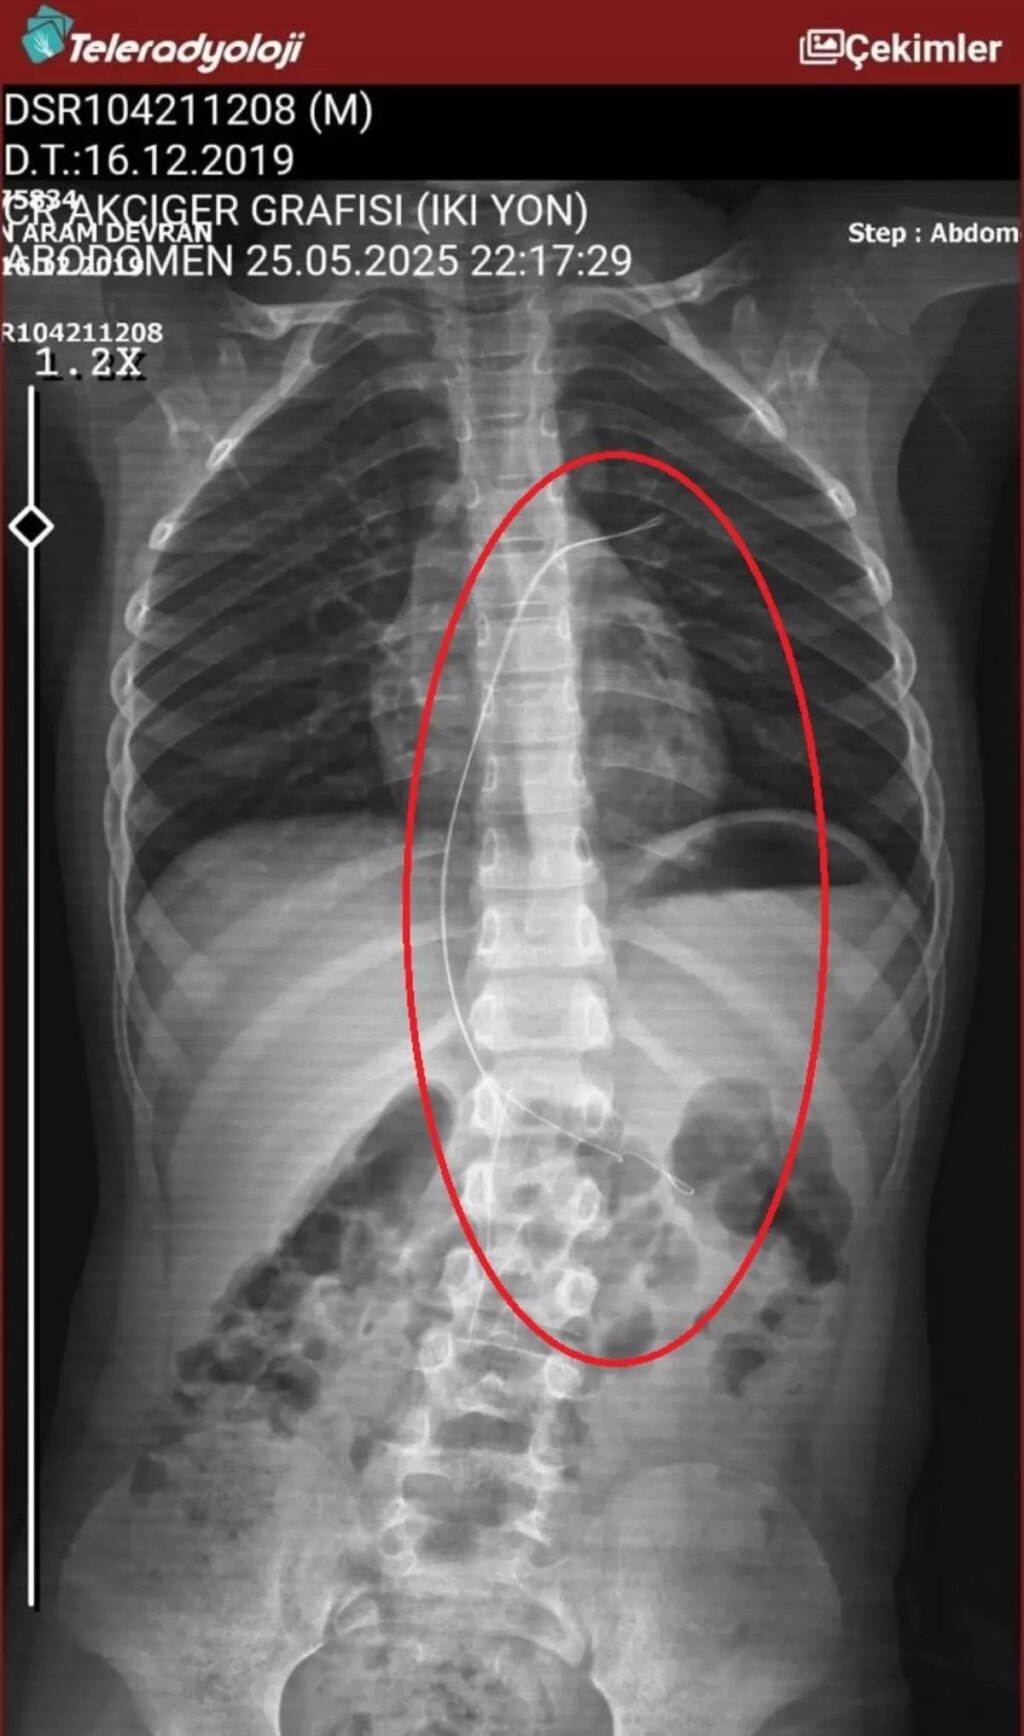

ŞIRNAK'ta piknikte salatalık kesimi yuttuktan sonra öksürük ve kusma şikayetleriyle hastaneye götürülen Aram Devran Ötün'ün (6), 3 yıl evvel Stevens- Johnson sendromu nedeniyle tedavi gördüğü sırada damar yoluna takılan 18 santimetrelik kateterin bedeninde unutulduğu ortaya çıktı.

ŞIRNAK’ta piknikte salatalık kesimi yuttuktan sonra öksürük ve kusma şikayetleriyle hastaneye götürülen Aram Devran Ötün’ün (6), 3 yıl evvel Stevens- Johnson sendromu nedeniyle tedavi gördüğü sırada damar yoluna takılan 18 santimetrelik kateterin bedeninde unutulduğu ortaya çıktı. Öğüt, 5,5 saat süren riskli bir ameliyatla kateterden kurtuldu.

Şırnak’ta yaşayan Semra (37) ve Mehmet Ötün (40) çiftinin oğulları Aram Devran Ötün, mayıs ayında piknikteyken salatalık modülü yuttuktan sonra öksürük ve kusma şikayetleri görülünce Şırnak Devlet Hastanesi’ne götürüldü. Burada çekilen röntgen ve MR’da Aram’ın bedeninde kateter unutulduğu görüldü. Diyarbakır’daki Gazi Yaşargil Eğitim ve Araştırma Hastanesi Bayan Doğum ve Çocuk Ek Binası’na sevk edilen Aram, 5,5 saat süren riskli bir ameliyata alınarak 18 santimetre uzunluğundaki kateter çıkarıldı. Ameliyat sonrası yapılan incelemelerde kateterin kalp kapakçığına ve ciğerlerine ziyan verdiği belirlendi.

Oğlunun piknikte salatalık modülü yuttuktan sonra daima öksürmeye ve kusmaya başladığını söyleyen Semra Ötün, “Çocuğum 3 yıl evvel Steven Johnson sendromu hastalığına yakalandı. Milyonda bir görülen antibiyotikten kaynaklı bir hastalık. Hekimler o denli söyledi. Bizi hemen Diyarbakır Dicle Üniversitesi Çocuk Hastanesi kısmına sevk ettiler. 1 ay ağır bakım sürecimiz oldu. 28 gün ağır bakımda, 3 günde serviste kaldı. Damar yolundan, kasıktan serum taktılar. Kateter denilen tel çocuğun bedeninde bırakılıyor. Biz taburcu olduğumuzda fark edilmiyor. 3 yılın sonunda biz bunu fark ettik. Pikniğe gittik. Oğlum salatalık kesimi yuttu ve salatalık modülünden sonra akşama kadar öksürdü. Hiçbir biçimde durmadı. Kusuyordu. Ben şüphelenmeye başladım. Çocuğum olağan değildi. Sonra eşime danıştım. Akşam 21.00 civarında acile götürdük. Röntgeni ve MR’ı çekildi. Tuhaf bir şey olduğunu anladık. Doktor röntgeni gösterdi. Tel kalmıştı. Çok berbat bir biçimde. Acil tabibi sinema çektikten sonra bize bir tel modülünü gösterdi. Bizi bekletmeden Diyarbakır’a sevkimizi verdiler. Diyarbakır Gazi Yaşargil Eğitim ve Araştırma Hastanesi Bayan Doğum ve Çocuk Ek Binası’na gittik. Çocuğun kasıklarından anjiyo yolu ile teli çıkaracaklarını ancak riskli bir ameliyat olduğunu söylediler. O süreçte çocuk nitekim daima yoruluyordu. İkide bir oturuyordu. ‘Anne çok yoruldum, karnım ağrıyor’ diyordu. Ben ağrı kesiciler ile geçiştirmeye çalışıyordum. Bu telin 3 yıl boyunca çocuğumda kaldığını öğrendim. Ailece yıkıldık” diye konuştu.